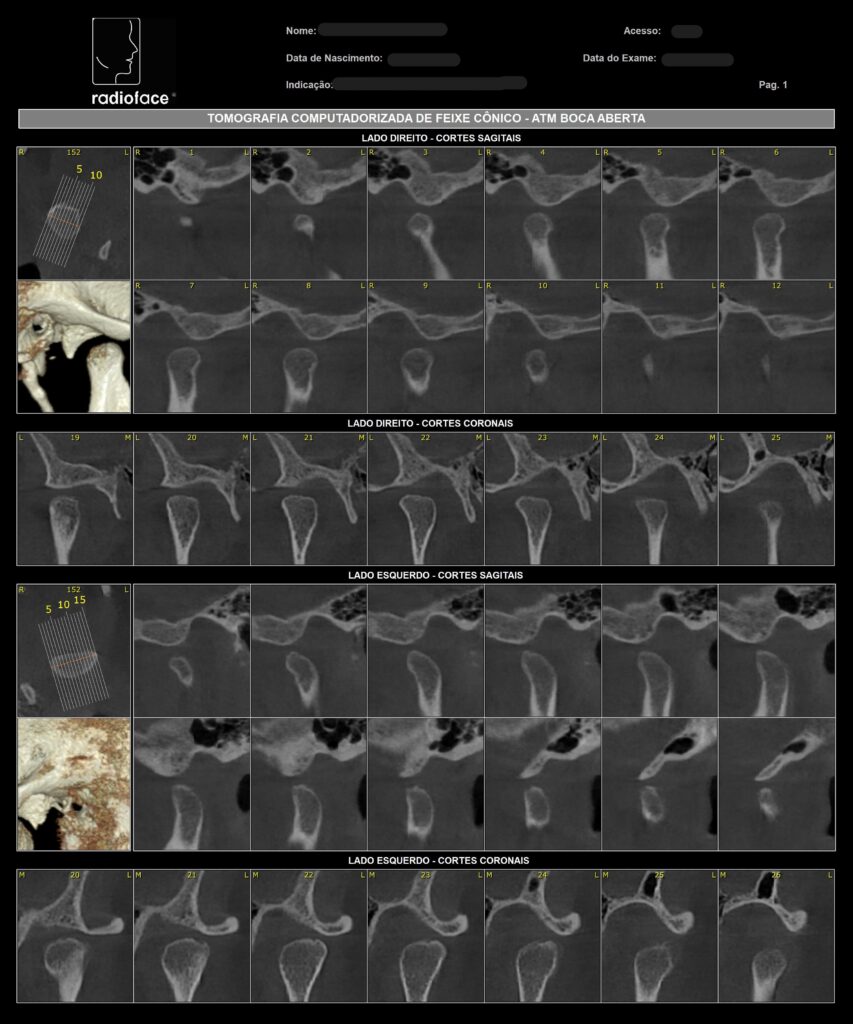

Radiografia de ATM

Tomografia Computadorizada

Exame Tridimensional dos Maxilares

Tomógrafo de Altíssima Resolução